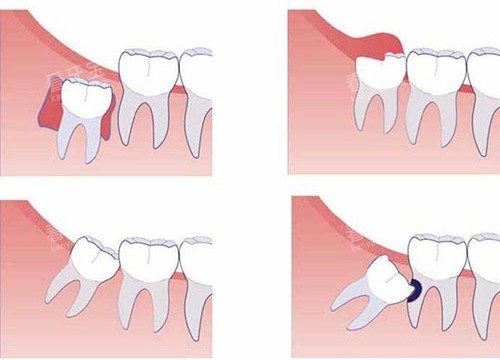

在正式前往拔牙前,我搜集了各类关于智齿的资料。原来智齿又称为第三磨牙,是口腔内比较靠近喉咙的牙齿。由于现代人的颌骨逐渐变窄,智齿经常没有足够的空间正常萌出,从而导致各种问题。我的情况正是如此——右下方的智齿只露出一个小角,大部分被牙龈覆盖,极易藏匿食物残渣,引起冠周炎。

在问询环节,医生详细询问了我的健康状况和药物过敏史,并安排了口腔X光检查。当看到X光片上我那颗倾斜生长的智齿时,医生耐心解释道:“你的这颗智齿属于前倾阻生,牙根形态较为复杂,拔除会有一定难度,但不用太过担心,整个过程都会在麻醉下进行。”

拔牙难度:简单萌出的智齿拔除后可能只有轻微肿胀,甚至不明显;而埋伏阻生智齿,特别是需要切开牙龈、去除部分骨质的复杂拔牙,术后肿胀会更为明显。